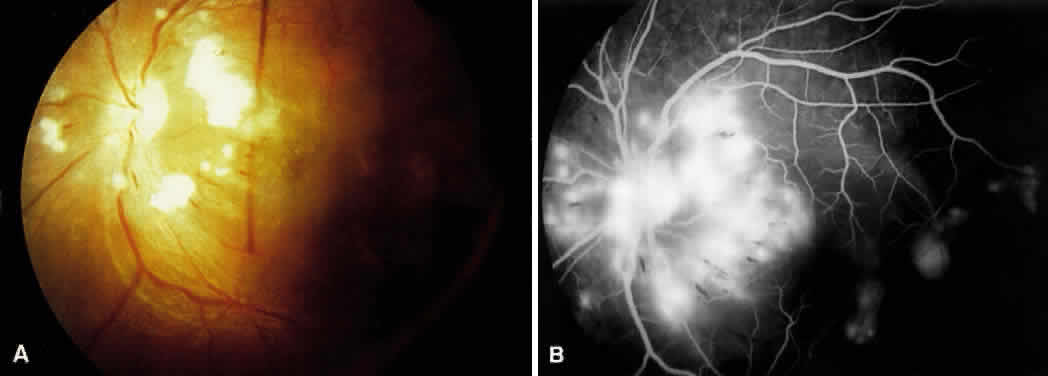

| In malignant hypertension, one of the earliest changes seen is optic nerve

head edema6,32: Clinical Findings in Neuropathy

The clinical appearance is indistinguishable from other causes of optic nerve head swelling, such as elevated intracranial pressure (Fig. 10). The mechanism of disc swelling remains controversial. In Tso and Jampol's study of baboons,8 the edema was believed to be the result of an accumulation of axoplasmic components. However, they could not determine whether this accumulation was related to ischemia or to some mechanical phenomena. Kishi and associates6 demonstrated axonal hydropic swelling that was secondary to ischemia. They later concluded that the ischemia produced was related to vasoconstriction of the peripapillary choroidal and optic nerve head vessels.11,32 The direct vasoconstrictive and occlusive properties seen in hypertensive choroidopathy lead to ischemic changes in the optic nerve head because it receives most of its blood supply from the peripapillary choroidal vessels.11,32,33 Further, vascular endothelial substances can diffuse easily into the optic nerve head from the surrounding choroidal bed and cause vasoconstriction of the optic nerve head vessels.11,32,33 Late findings seen in hypertensive neuropathy are optic nerve head pallor and atrophy resulting from chronic ischemia. The clinician must be careful to rule out other possible causes of these findings, including anterior ischemic optic neuropathy and temporal arteritis when evaluating patients for hypertensive optic neuropathy. |